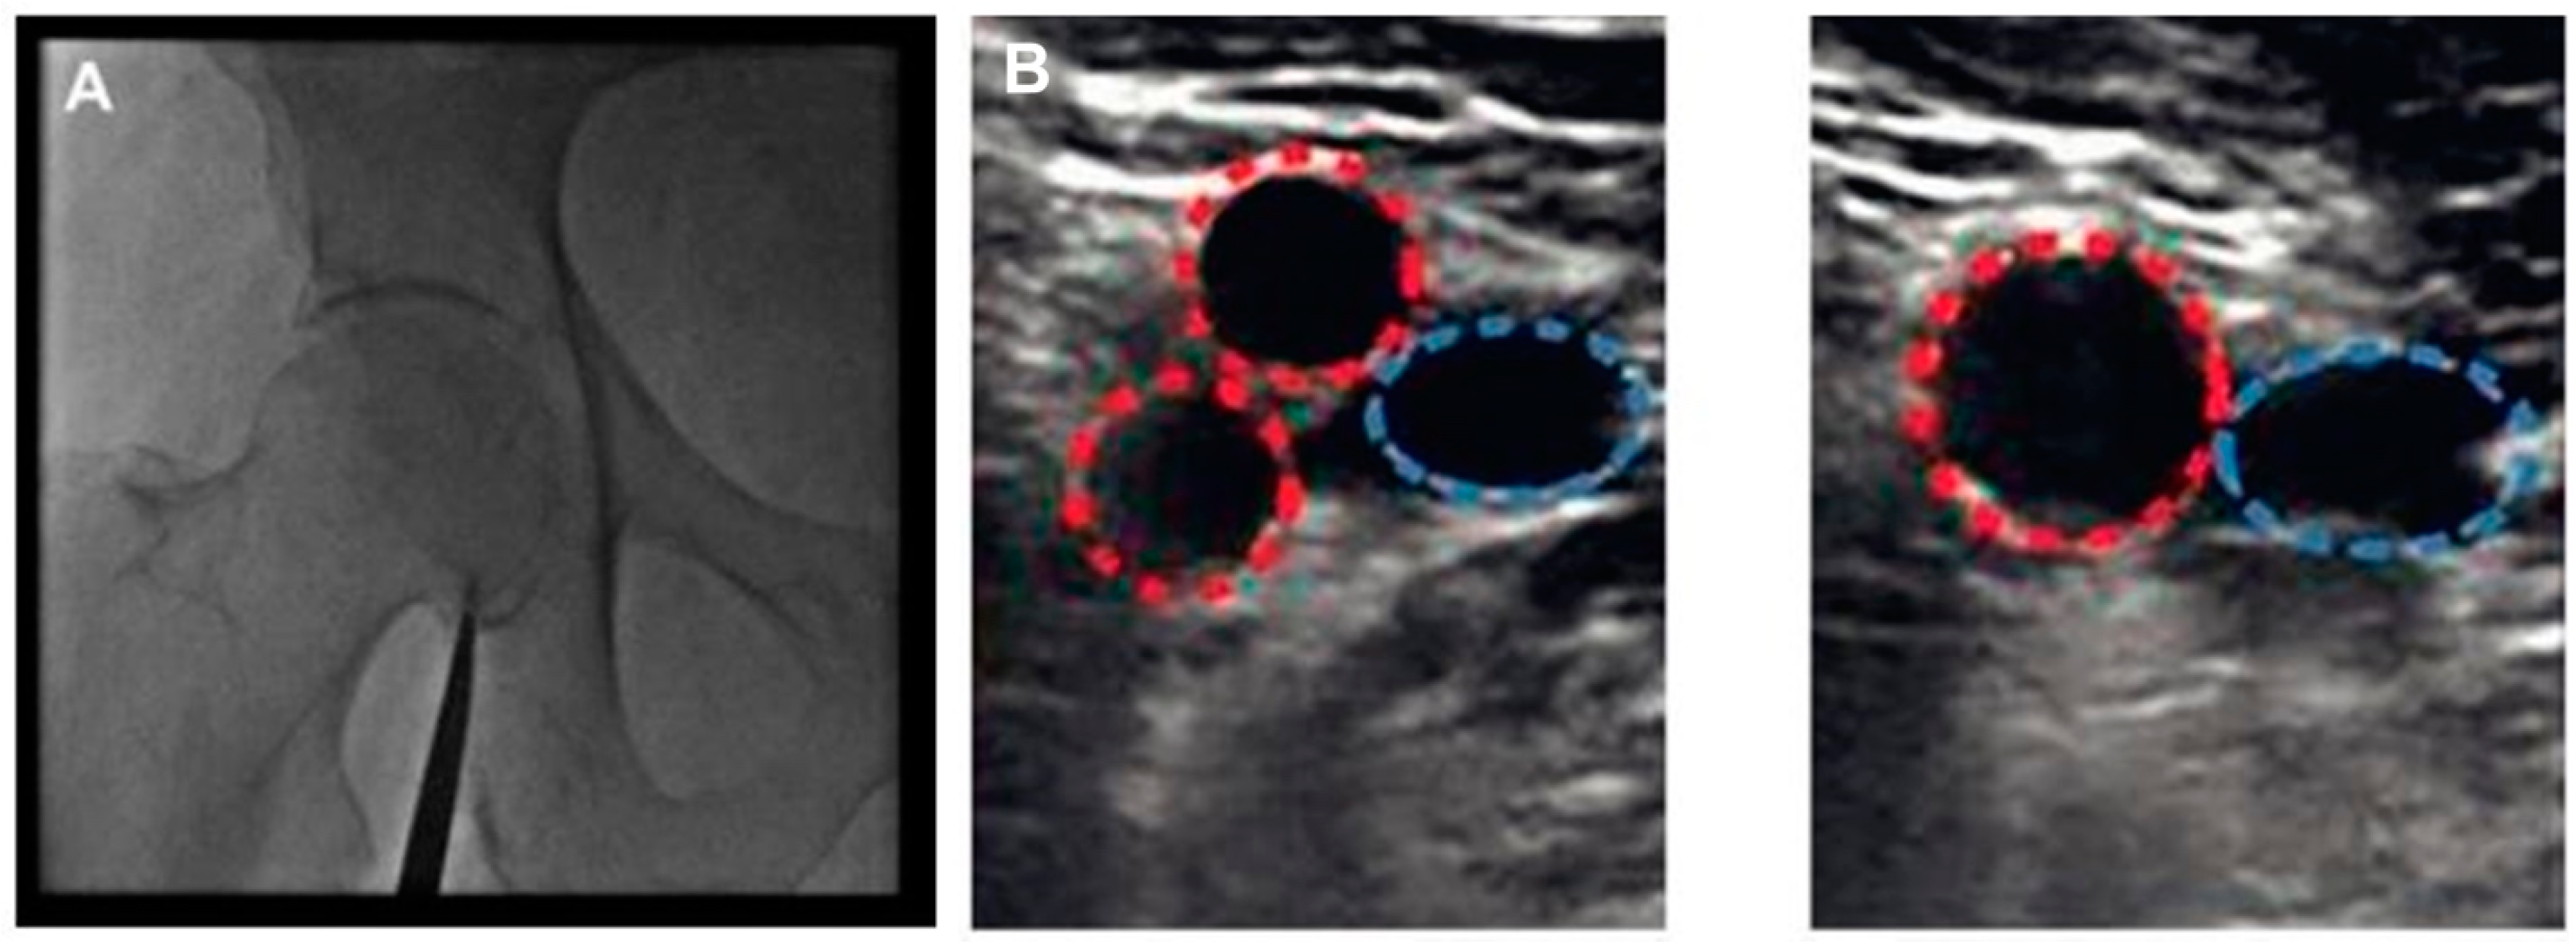

- Damluji, A.A.; Nelson, D.W.; Valgimigli, M.; Windecker, S.; Byrne, R.A.; Cohen, F.; Patel, T.; Brilakis, E.S.; Banerjee, S.; Mayol, J.; et al. Transfemoral approach for coronary angiography and intervention: A collaboration of international cardiovascular societies. JACC Cardiovasc. Interv. 2017, 10, 2269–2279. [Google Scholar] [CrossRef]

- Brilakis, E.S. Manual of Percutaneous Coronary Interventions: A Step-by-Step Approach; Elsevier/Academic Press: London, UK, 2020. [Google Scholar]

- Schnyder, G.; Sawhney, N.; Whisenant, B.; Tsimikas, S.; Turi, Z.G. Common femoral artery anatomy is influenced by demographics and comorbidity: Implications for cardiac and peripheral invasive studies. Catheter. Cardiovasc. Interv. 2001, 53, 289–295. [Google Scholar] [CrossRef]

- Sandoval, Y.; Burke, M.N.; Lobo, A.S.; Lips, D.L.; Seto, A.H.; Chavez, I.; Sorajja, P.; Abu-Fadel, M.S.; Wang, Y.; Poulouse, A.; et al. Contemporary Arterial Access in the Cardiac Catheterization Laboratory. JACC Cardiovasc. Interv. 2017, 10, 2233–2241. [Google Scholar] [CrossRef]